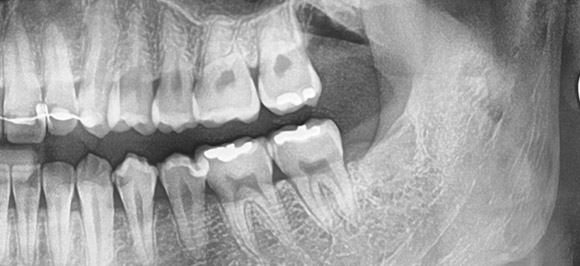

사랑니발치

18세 전·후로 자라는 사랑니, 이름과 달리 대부분은 골칫덩이로 자라…

혹시나 기형 혹은 잇몸 안에서 자라는 매복이라면?

주변은 물론 구강 전체 악영향을 줄 수 있어, 발치가 필요!